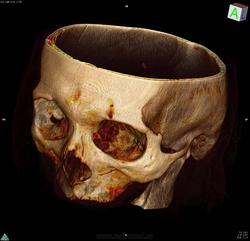

я дефект вижу. вот он, даже на реконструкции прекрасно виден.

Насчет того что обязательно "УЖЕ" должны быть осложнения вроде абсцесса, на мой взгляд это совершенно не обязательно. они могут возникнуть через 2 дня, а могут через полгода. В статье, что Вы привели как раз таки написано, что в основе патогенеза мукоцеле - асептическое воспаление.

дефекта нижней стенки вы тоже не видите? ячейки решетчатой кости на Ваш взгляд в полном порядке?

Приложения:

izobrazhenie_3d-renderinga_obyoma.jpg

Уважаемый, Коллега! Согласен с лизисом и деструкцией стенок ячеек решетчатой кости; но этот процесс возможен и при банальном воспалительном процессе.  Какая дальнейшая судьба пациентки?